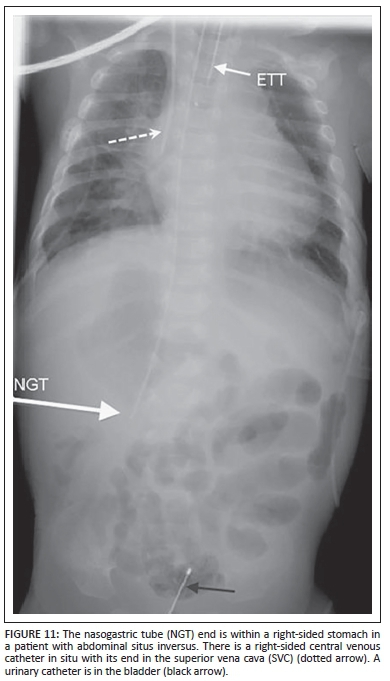

Nasogastric tube (NGT)

Uses: The NGT is inserted for the aspiration of gastric contents, gastric decompression or feeding the patient. The tip should lie within the stomach.

Complications

The NGT can be misplaced in the tracheobronchial tree (Figure 10). Perforation of the oesophagus or stomach is extremely uncommon, but can occur, particularly in premature infants.7 A coiled NGT in a proximal oesophageal pouch is important to recognise in oesophageal atresia.2 In neonates with left-sided congenital diaphragmatic hernia, the NGT tip is most commonly positioned at the gastro-oesophageal junction or within the left hemithorax. An NGT deviating to the right is seen in a patient with heterotaxy syndrome and abdominal situs (Figure 11).